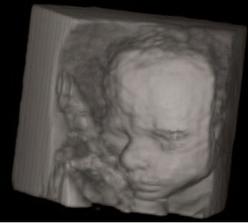

6.12.2007 - jedu na 3D ultrazvuk